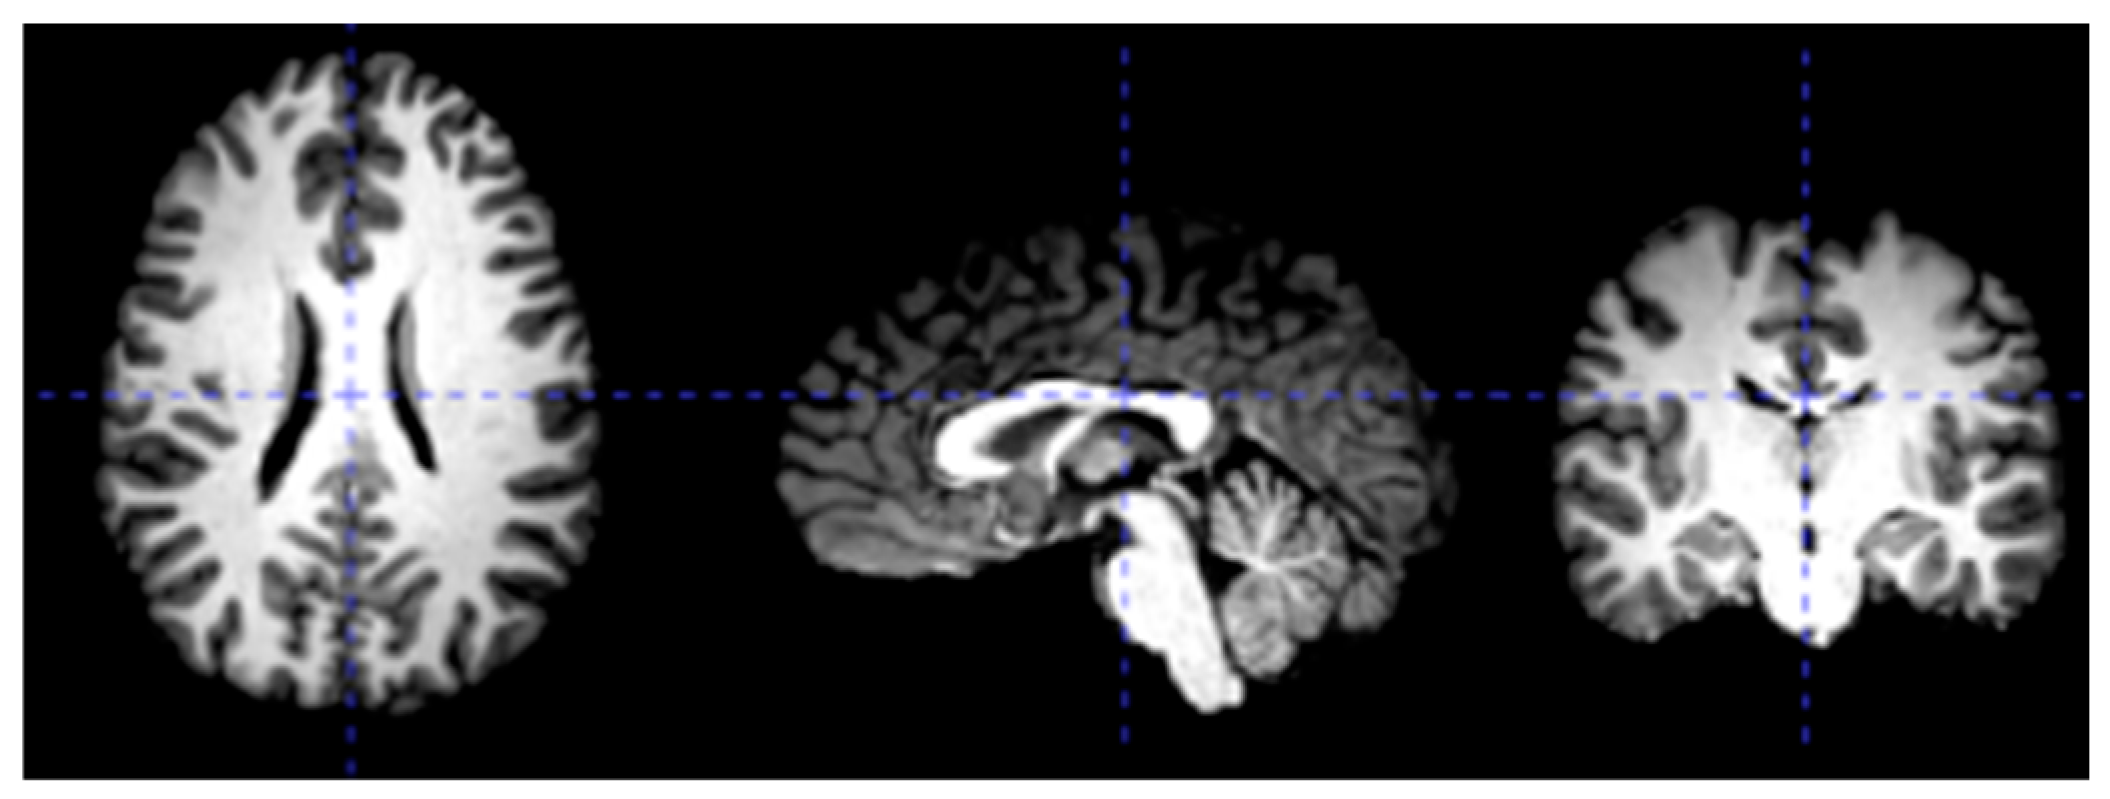

3.2. Data Preprocessing